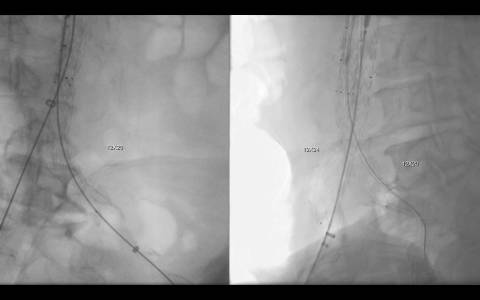

A avaliação por tomografia computadorizada evidenciou um aneurisma infra-renal de colo hostil e acessos vasculares com muita ateromatose. Diante do contexto clínico e de imagem foi optado pelo tratamento endovascular com endoprótese de baixo perfil Incraft CORDIS e técnica de Snorkel Grafts com stents Palmaz CORDIS para as artérias renais.